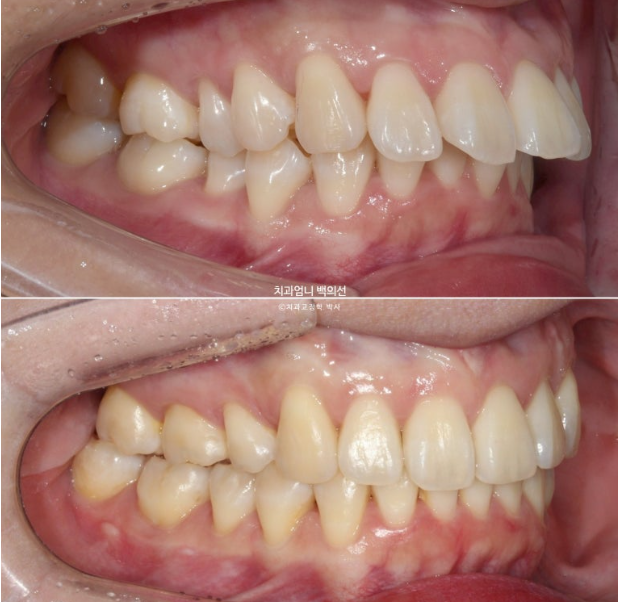

윗니도 많이 뻗쳐 있습니다.

배열도 좋지 않아서 발치교정 권유드렸습니다.

위 작은어금니 2개 발치 아래는 매복사랑니 발치 후 작은 어금니 발치 없이 미니스크류를 심고 후방이동 하는 계획입니다.

교정장치는 인비절라인이며 23년 3월에 장치를 끼기 시작했습니다.

과개교합은 잘 개선이 되었습니다.

미니스크류와 고무줄의 조합은 인비절라인 발치교정이 성공으로 가는 노하우 입니다.

발치공간이 아직 남아있고 앞니 각도의 개선이 더 필요합니다.

아래 어금니들은 사랑니 공간으로 잘 이동했습니다.

개선된 과개교합과 일치된 중심선

앞니 뻗침도 많이 좋아졌습니다.